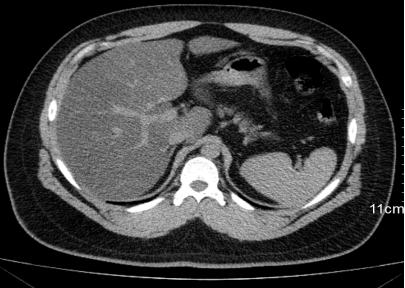

患者既往肝硬化病史,体检发现肝右叶占位,进一步增强CT检查如图示。关于该患者肝右叶占位描述正确的是

选项:

A: 发病与乙型肝炎和肝硬化密切相关

B: 大部分患者AFP升高

C: 强化方式为“快进快出”

D: 有“假包膜”

答案: 【 发病与乙型肝炎和肝硬化密切相关;

大部分患者AFP升高;

强化方式为“快进快出”;

有“假包膜”】

患者,女性,58岁,既往肺癌病史,行增强CT检查,如图示。该患者转移部位有

A: 肝

B: 胆囊

C: 肾上腺

D: 肾

答案: 【 肝;

肾上腺】